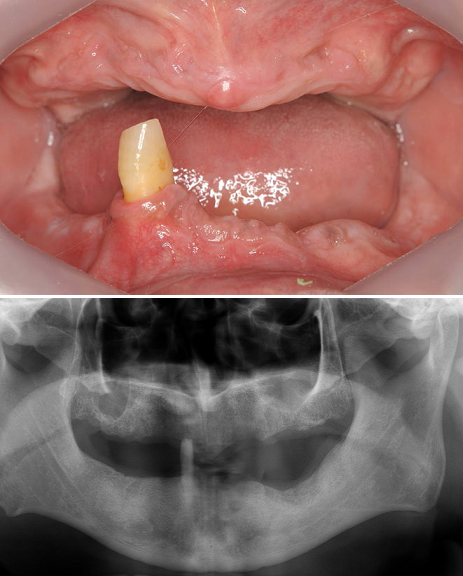

歯がなくなり、骨がやせてしまった場合は、骨を増やす処置をしてインプラント治療をしなければ下図のような審美的に良くない結果になります(他院で治療を受け、再治療を行うことになった患者さん)。

したがって、このようにならないように、やせた骨を回復させるために骨造成が必要となり、当院では、自家骨移植(ご自分の下顎骨の一部を移植します)、歯槽骨延長術(詳細は後述)を単独あるいは併用して、審美的に良好な結果を得ています。